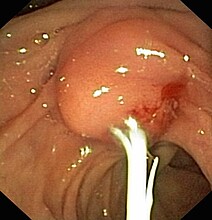

Bild rechts: Papilla Duodeni oder Sphinkter Oddi: Mündung von Hauptgallengang (Ductus choledochus) und Bauchspeicheldrüsengang (Ductus pancreaticus) in den Zwölffingerdarm (Duodenum).